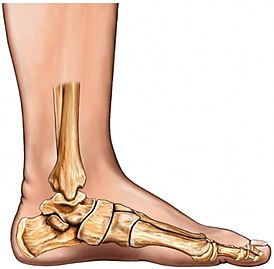

Плоскосто́пие — изменение формы стопы, характеризующееся опущением её продольного и поперечного сводов. Различается поперечное и продольное плоскостопие, возможно сочетание обеих этих форм.

Основные понятия

Стопа человека представляет собой уникальную механическую конструкцию, функционирование которой должно обеспечивать хорошую переносимость статической и динамической нагрузки под весом собственного тела в течение длительного времени. Обеспечение рессорной функции стопы обеспечивается анатомическим строением, наличием продольного и поперечного свода стопы, образованных костями предлюсны (совокупность небольших костей стопы, заключённых между костями голени (больше- и малоберцовой) проксимально и костями плюсны — дистально. Сустав, образующийся между костями голени и предплюсной (точнее — её таранной костью) называется голеностопным) и плюсны (средний отдел стопы у позвоночных, расположенный между предплюсной и пальцами. Как правило, состоит из трубчатых костей, числом равных числу пальцев). В норме при динамической нагрузке (ходьба, бег) происходит перекат через стопу, при котором максимальное давление приходится последовательно на пятку, наружный край стопы и головки первой и пятой плюсневых костей. В норме участки гиперкератоза кожи определяются только в этих зонах. Медиальный край подошвы, по которому проходят сухожилия сгибателей пальцев и супинаторов стопы, непосредственно с опорой не соприкасается[1].